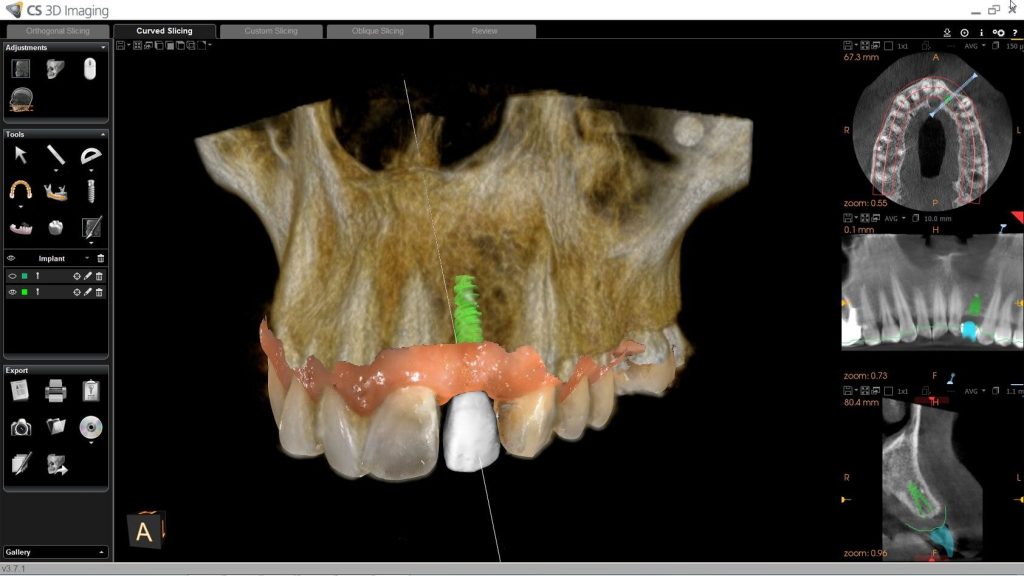

Oltre allo scanner digitale, il moderno studio dentistico dispone di TAC 3D che permettono di poter valutare in tre dimensioni l’osso a disposizione per poter riavere i denti fissi o per fare una diagnosi accurata dove le ortopanoramiche o le classiche lastrine non arrivano. Questa macchina è a basso dosaggio ed è fondamentale il suo utilizzo per un attenta pianificazione, in modo da non avere sorprese durante le fasi chirurgiche.